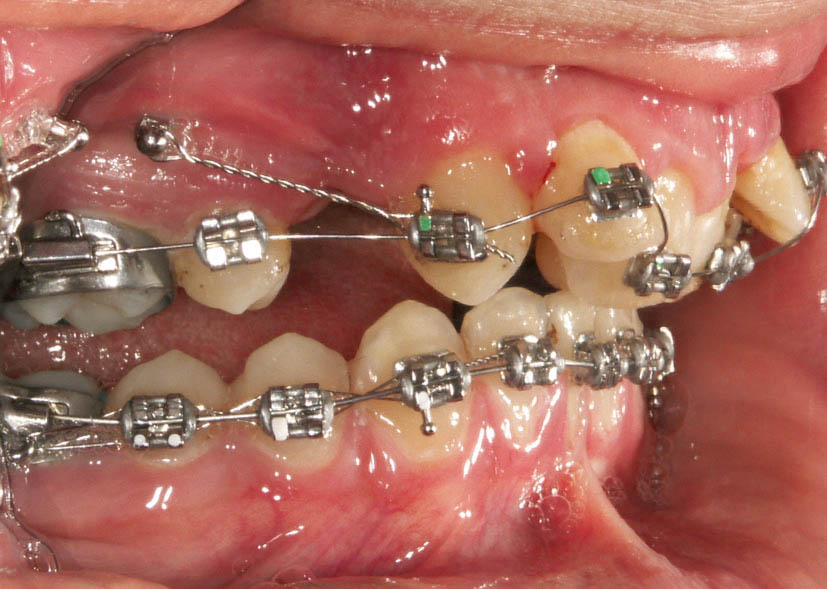

وقتی 7mm یا همان یک کاسپ کامل کلاسII است (شکل 107-2) فقط پرمولر بالا کشیده میشود. هدف رسیدن به یک کاسپ کامل کلاسII است. در ابتدای درمان هم همین اکلوژن را دارید، پس بعد از کشیدن پرمولر اول، تا انتهای درمان نباید خلفیهای بالا حرکت مزیالی بکنند، لذا باید مینی اسکرو بگذارید (شکل 108-2) و تمام فشارها را به آن اعمال کند. وقتی هیچ فشار مزیاله کنندهای روی مولرها نباشد پس حرکتی نخواهند نمود و تا انتهای درمان همان جا میمانند و ارتودنسی به صورت یک کاسپ کامل کلاسII تمام میشود (شکل 109-2).

شکل 108-2: قرار دادن مینی اسکرو در یک کاسپ کامل کلاسII

شکل 109-2: نتیجه درمان یک کاسپ کامل کلاسII تمام میشود